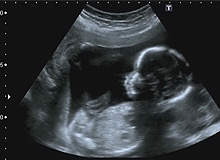

In February 2010, the independent advisory group on non-ionising radiation (AGNIR) published a report that examined the health risks arising from exposure to ultrasound. While there is no evidence that the scan does any harm to expectant mothers, it did provoke some uncertainties about the effect it could have on the developing brain of the foetus.

Levine confirms that it is the safest way of looking at the developing foetus without exposing the mother or baby to the risks of radiation. The routine scans performed at ten-13 weeks and 18-20 weeks can determine the baby’s definite gestational age, identify multiple pregnancies, inform parents about the baby’s growth and placental health, and identify many developmental and structural abnormalities. Of course, there are several stipulations medical professionals must adhere to when performing an ultrasound scan.